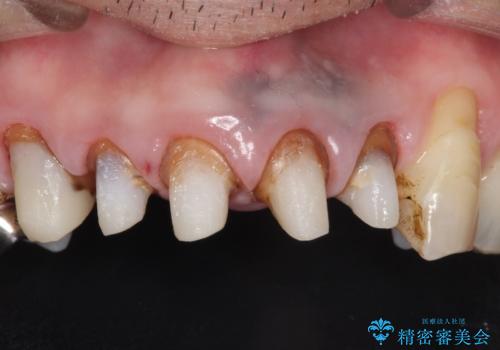

- 上の前歯の根元が黒くなっているので、再治療をしたいとのことで来院された患者様です。

レントゲンを撮影すると、適合不良のかぶせ物が装着されており、根の治療も不十分であることが確認されました。

適合不良のかぶせ物をすべて除去して、根の中の治療から再治療を行うこととなりました。

適合不良のかぶせ物が装着されていた歯は、内部がやはり虫歯になっていました。

かぶせ物だけではなく見えないところも、精密な治療をすることが重要となります。